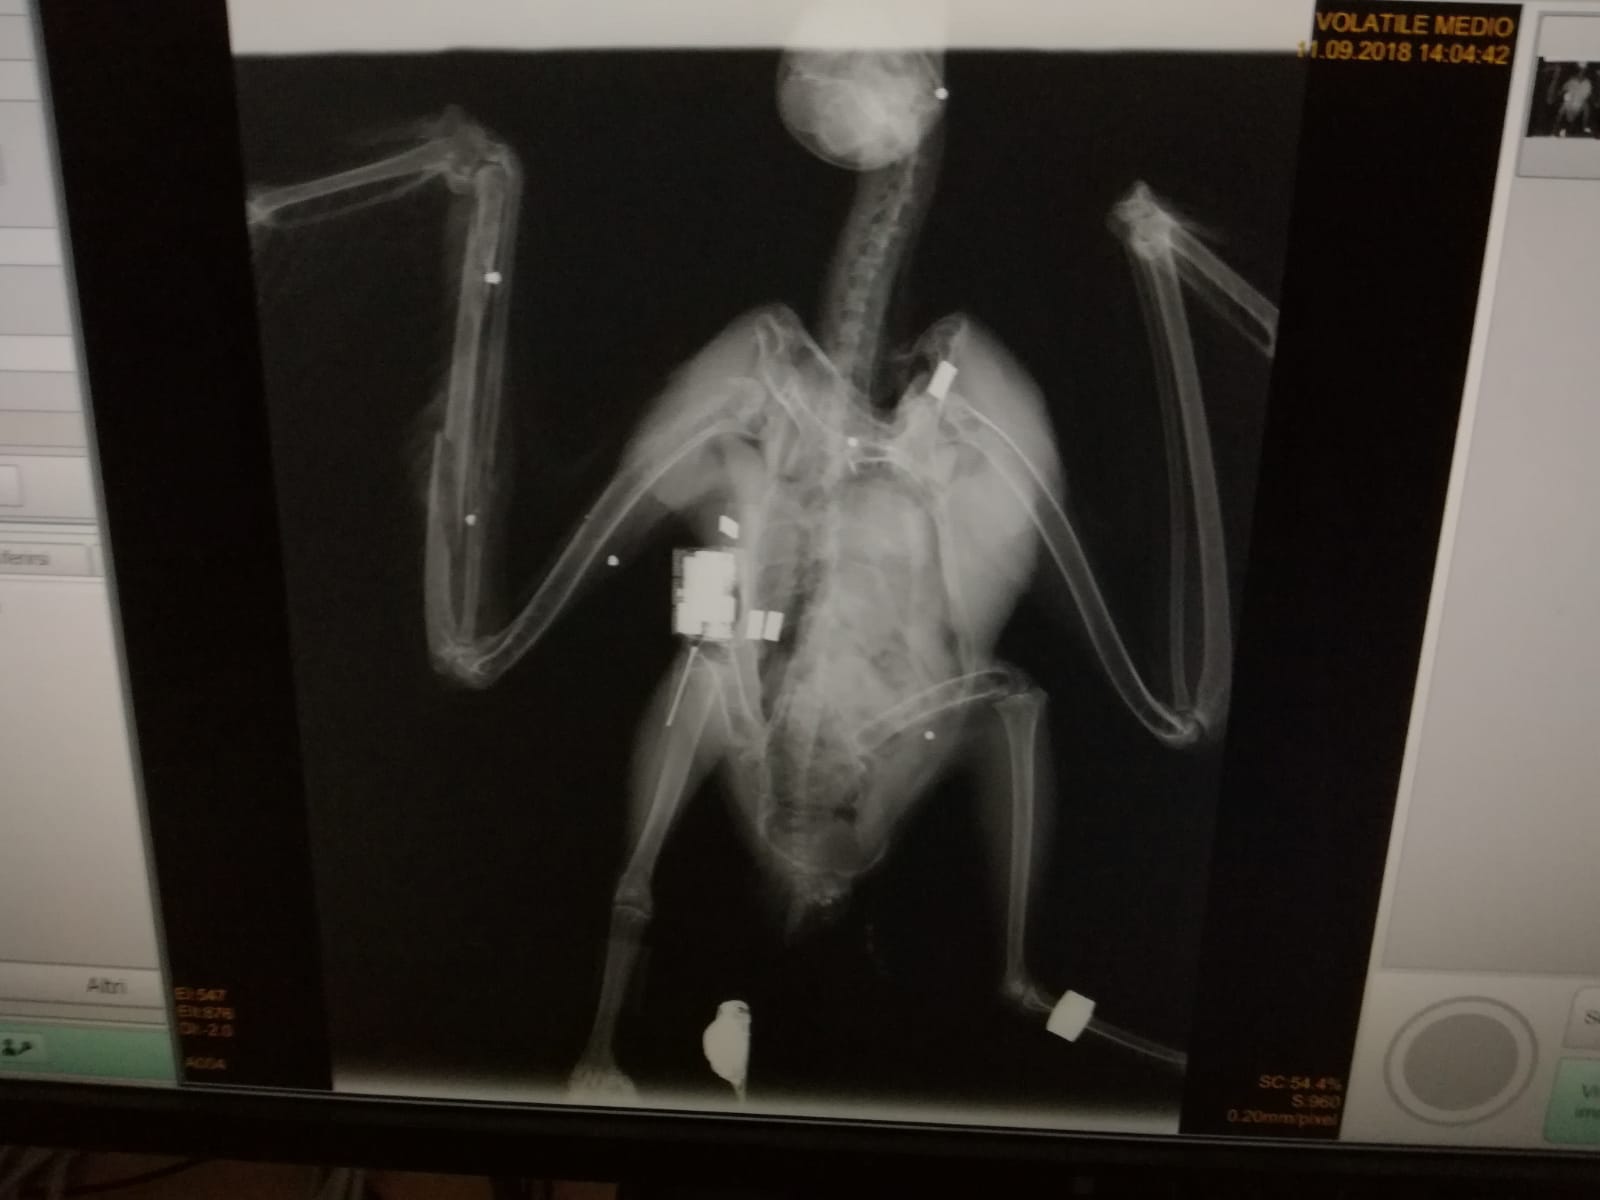

Grazie ai dati del trasmettitore GPS/GSM

con cui le due giovani erano state equipaggiate prima del rilascio è stato

possibile scoprire e denunciare questo grave atto di bracconaggio e consentirne

il recupero del corpo grazie alla segnalazione e al successivo intervento dei

Carabinieri del Servizio CITES della

Sicilia che l’hanno prontamente conferita presso l’Istituto Zooprofilattico

della Sicilia per le analisi necroscopiche permettendo così di evidenziare la

presenza di 7 pallini nel corpo.

| Radiografia |